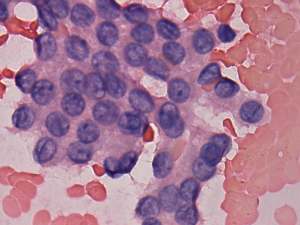

Cytology. Papillary cancer was diagnosed in the nodule in the left lobe and a metastasis of the thyroid cancer into one of the enlarged lymph nodes.

Histopathology. Papillary cancer in the left lobe with metastasis to the lymph nodes, and hyperplastic nodules in the right lobe.